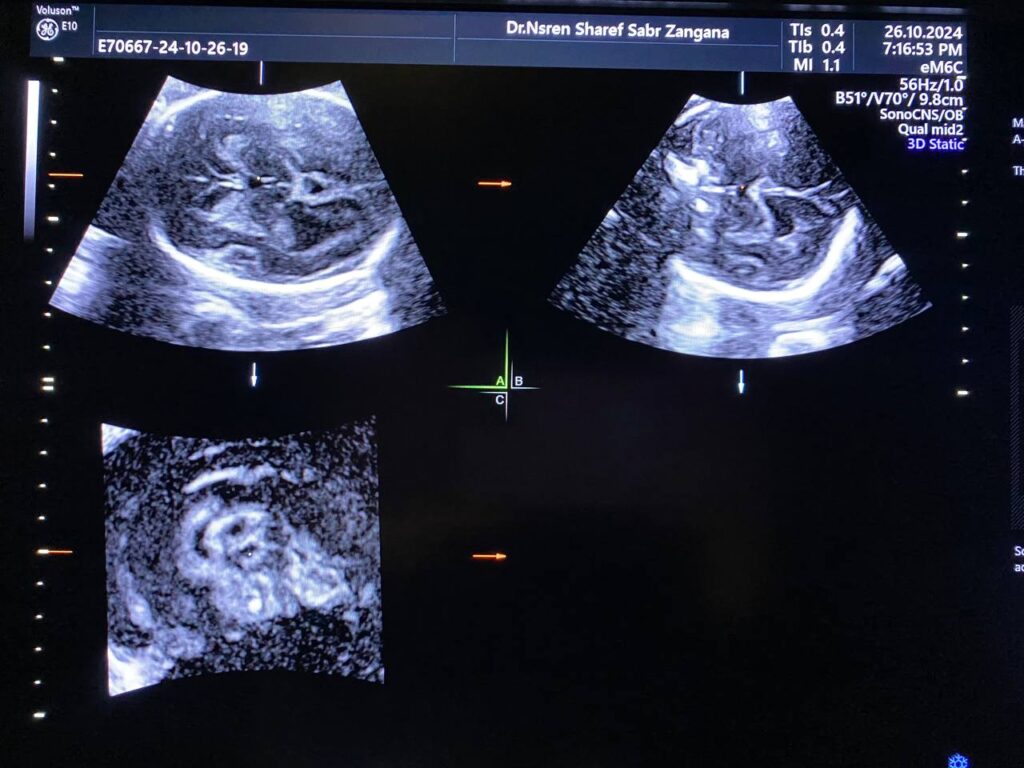

Brain: mild to moderate dilated lateral ventricles 16mm, with remaining cerebral mental about 13mm, dilated third ventricle, normal fourth ventricle, Picture mostly of Hydrocephaly due to aqueduct of Sylvius stenosis